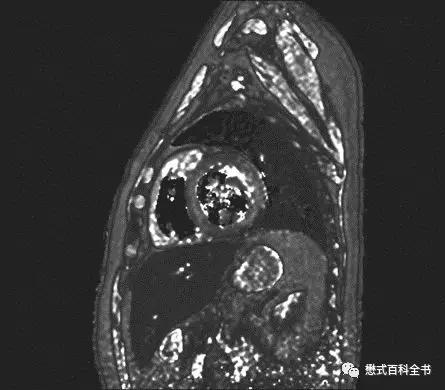

图1:心脏的T2 mapping

T2 mapping就是测量组织的T2值的一种磁共振定量技术,通过测量成像FOV内各个基本的体元(体素)的T2值,然后重建得到一副反映组织T2值分布的T2值图(T2 mapping)。

一般来讲T2 mapping在心脏磁共振中主要用于鉴别心肌缺血、炎症、脉管炎及相关的心肌水肿。